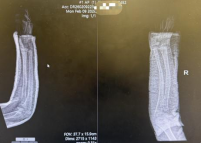

2月9日,4岁的小嘉佑被父亲紧紧抱在怀里来到了西安市红会医院手法复位室,孩子的右前臂明显肿胀、变形。接诊的张晓星医生立即进行体格检查,并安排影像学检查。X线片显示,小嘉佑为典型的儿童尺桡骨双骨折,骨折线横贯前臂中下段,骨折端不仅存在明显的侧方移位,还伴有一定程度的成角畸形。

复位后即刻复查的X线片正位片显示,桡骨与尺骨骨折端对位良好,侧方移位完全纠正;侧位片显示掌背侧成角畸形已有效矫正,力线接近正常。